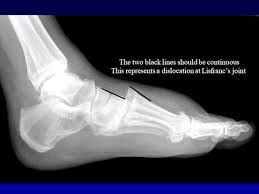

A Lisfranc fracture is a type of broken foot. The Lisfranc joint is the spot on top of your foot where the metatarsal bones (the bridges to your toes) connect to the rest of your foot. This is a complicated area of your foot. It’s where many bones, ligaments and tendons all come together to hold your foot’s arch in shape and help it move properly. Because so many parts of your foot meet up in one place, the Lisfranc joint is very important. It’s just like a busy highway on-ramp or main intersection in a city: A lot depends on a relatively small area to make everything work correctly. You can hurt any part of your Lisfranc joint. Lisfranc injuries are most commonly caused by an accident or some kind of trauma. Athletes can injure their Lisfranc joint playing sports, but even a small stumble or tripping throughout your day can cause an injury. Major traumas like car accidents and falling off a ladder also cause Lisfranc fractures and injuries. If you have a fracture, you broke at least one bone, but you can also tear or sprain any of the joint’s connective tissues.